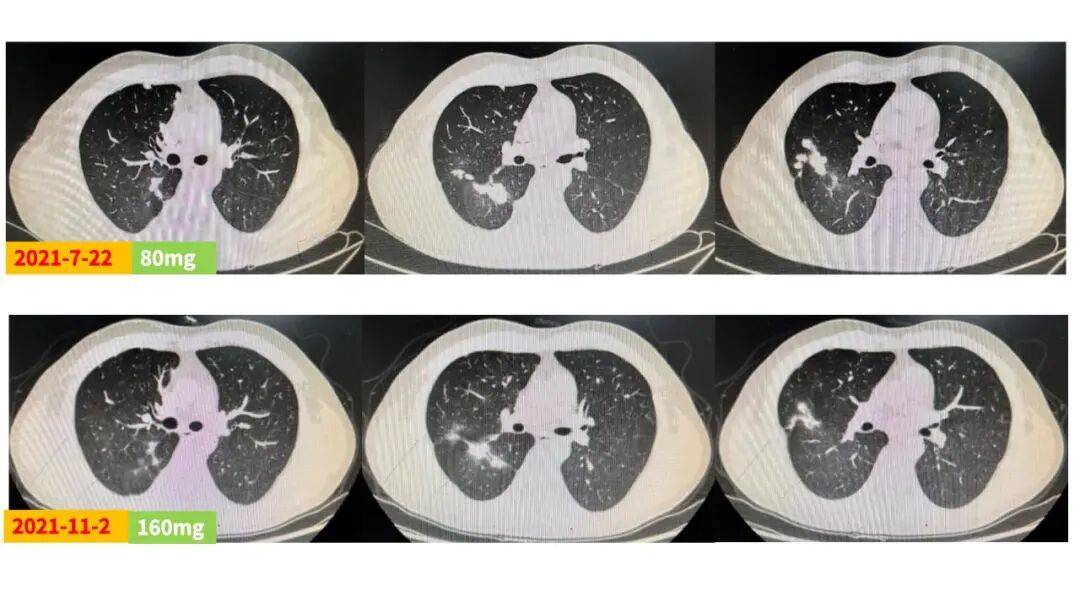

王韵 医生

该例EGFR ex20ins突变晚期NSCLC患者,合并胸膜转移,一线接受标准化疗联合贝伐珠单抗治疗后达SD,但在维持阶段提示疾病进展(PD)。在制定二线治疗方案时,主要考虑以下三大因素:第一,患者不具备条件参加EGFR 20ins相关临床试验;第二,患者不愿再接受化疗;第三,患者无法承担高昂治疗费用。综合考虑,最终选择了性价比高的第三代EGFR-TKI伏美替尼作为二线治疗方案。基于既往试验数据,高剂量伏美替尼疗效更佳,遂为患者进行剂量爬坡治疗。结果显示,伏美替尼80mg治疗两个月后疗效评估即达SD,且随着剂量增加,肺内病灶缓慢缩小,剂量240mg维持治疗期间病灶稳定,持续获益。同时治疗期间安全性良好,仅出现2级皮疹和睫毛增长,未见其他毒副反应。

近年来随着研究的不断深入与探索,三代EGFR-TKI在EGFR ex20ins突变晚期NSCLC前线治疗中展现出了巨大的潜力。FAVOUR研究[1]显示,伏美替尼240mg QD在 EGFR ex20ins突变晚期NSCLC初治和经治患者中的客观缓解率(ORR)分别为78.6%和46.2%,疾病控制率(DCR)分别为100%和92.3%,已有患者持续接受治疗并获得疾病缓解超26个月,且安全性良好。结合本例患者情况,为保证治疗的安全性及提高依从性,起始采用伏美替尼80mg剂量治疗,两个月即迅速达SD,患者快速恢复治疗信心,后续剂量爬坡至160mg和240mg剂量,肿瘤状况均持续稳定,最终采用240mg持续治疗,疾病控制稳定且安全性良好,仅出现2级皮疹和睫毛增长,充分展现了伏美替尼的出色疗效和安全性优势。